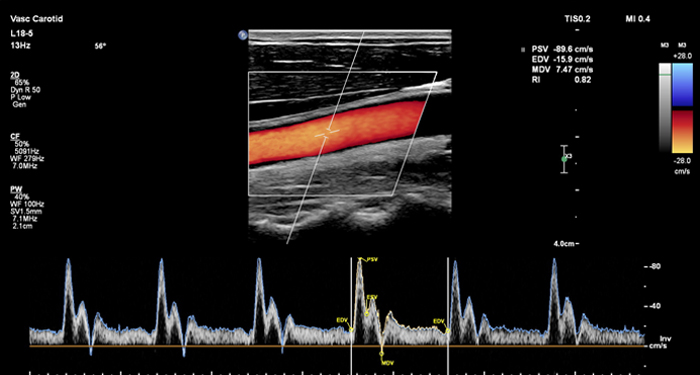

At the touch of a button, the new MaxVue high-definition display brings extraordinary visualisation of anatomy with 1,179,648 additional image pixels compared to a standard 4:3 display format mode. MaxVue enhances ultrasound viewing during interventional procedures and provides 38% more viewing area to optimise the display of dual, side/side, biplane, and scrolling imaging modes.

MaxVue offers a 38% greater viewing area.

MaxVue offers 1,179,648 additional image pixels compared to a standard 4:3 display format mode.